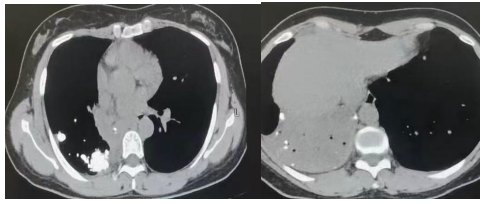

胸CT右中间段狭窄钙化影 右中下叶肺不张

入院支气管镜探查,可见右中间段明显狭窄开口直径约2-3mm,管口痰液堵塞。